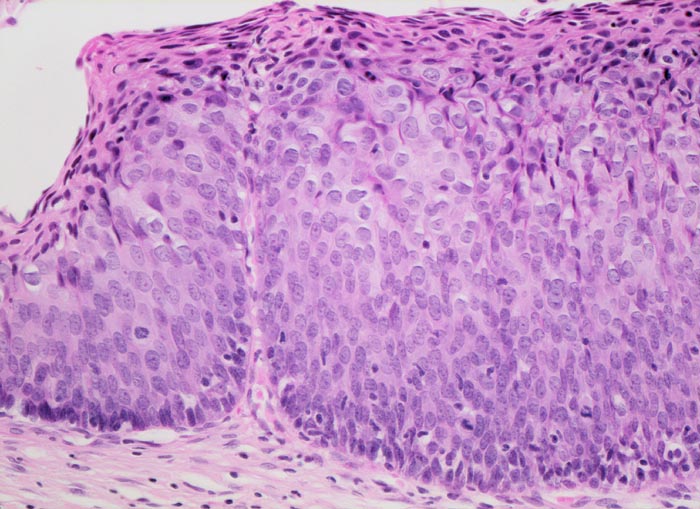

PathoPic – image database / PathoPic ID 4489 - mässige Dysplasie (CIN II) des Plattenepithels und Parakeratose

mässige Dysplasie (CIN II) des Plattenepithels und Parakeratose

Plattenepithel mit fehlender Ausreifung (wenig Zytoplasma, grosse Kerne) der dichtstehenden Zellen. Das Kernchromatin ist leicht vergröbert. Mitosen lassen sich in diesem mässig dysplastischem Epithel lediglich in der unteren Epithelhälfte nachweisen. An der Epitheloberfläche finden sich mehrere Schichten parakeratotischer Zellen mit kleinen kondensierten pyknotischen Kernen und dunkelrotem dichtem Zytoplasma.

Für die Dysplasie des Plattenepithels der Portio gibt es verschiedene Einteilungen:

WHO Einteilung:

kondylomatöse Läsion (HPV Infekt)

leichte Dysplasie (=CIN I)

mässige Dysplasie (=CIN II)

schwere Dysplasie und Carcinoma in situ (=CIN III)

Bethesda-Nomenklatur:

L-SIL (low grade squamous intraepithelial neoplasia=kondylomatöse Läsion oder leichte Dysplasie)

H-SIL (high grade squamous intraepithelial neoplasia=mässige Dysplasie, schwere Dysplasie oder Carcinoma in situ)